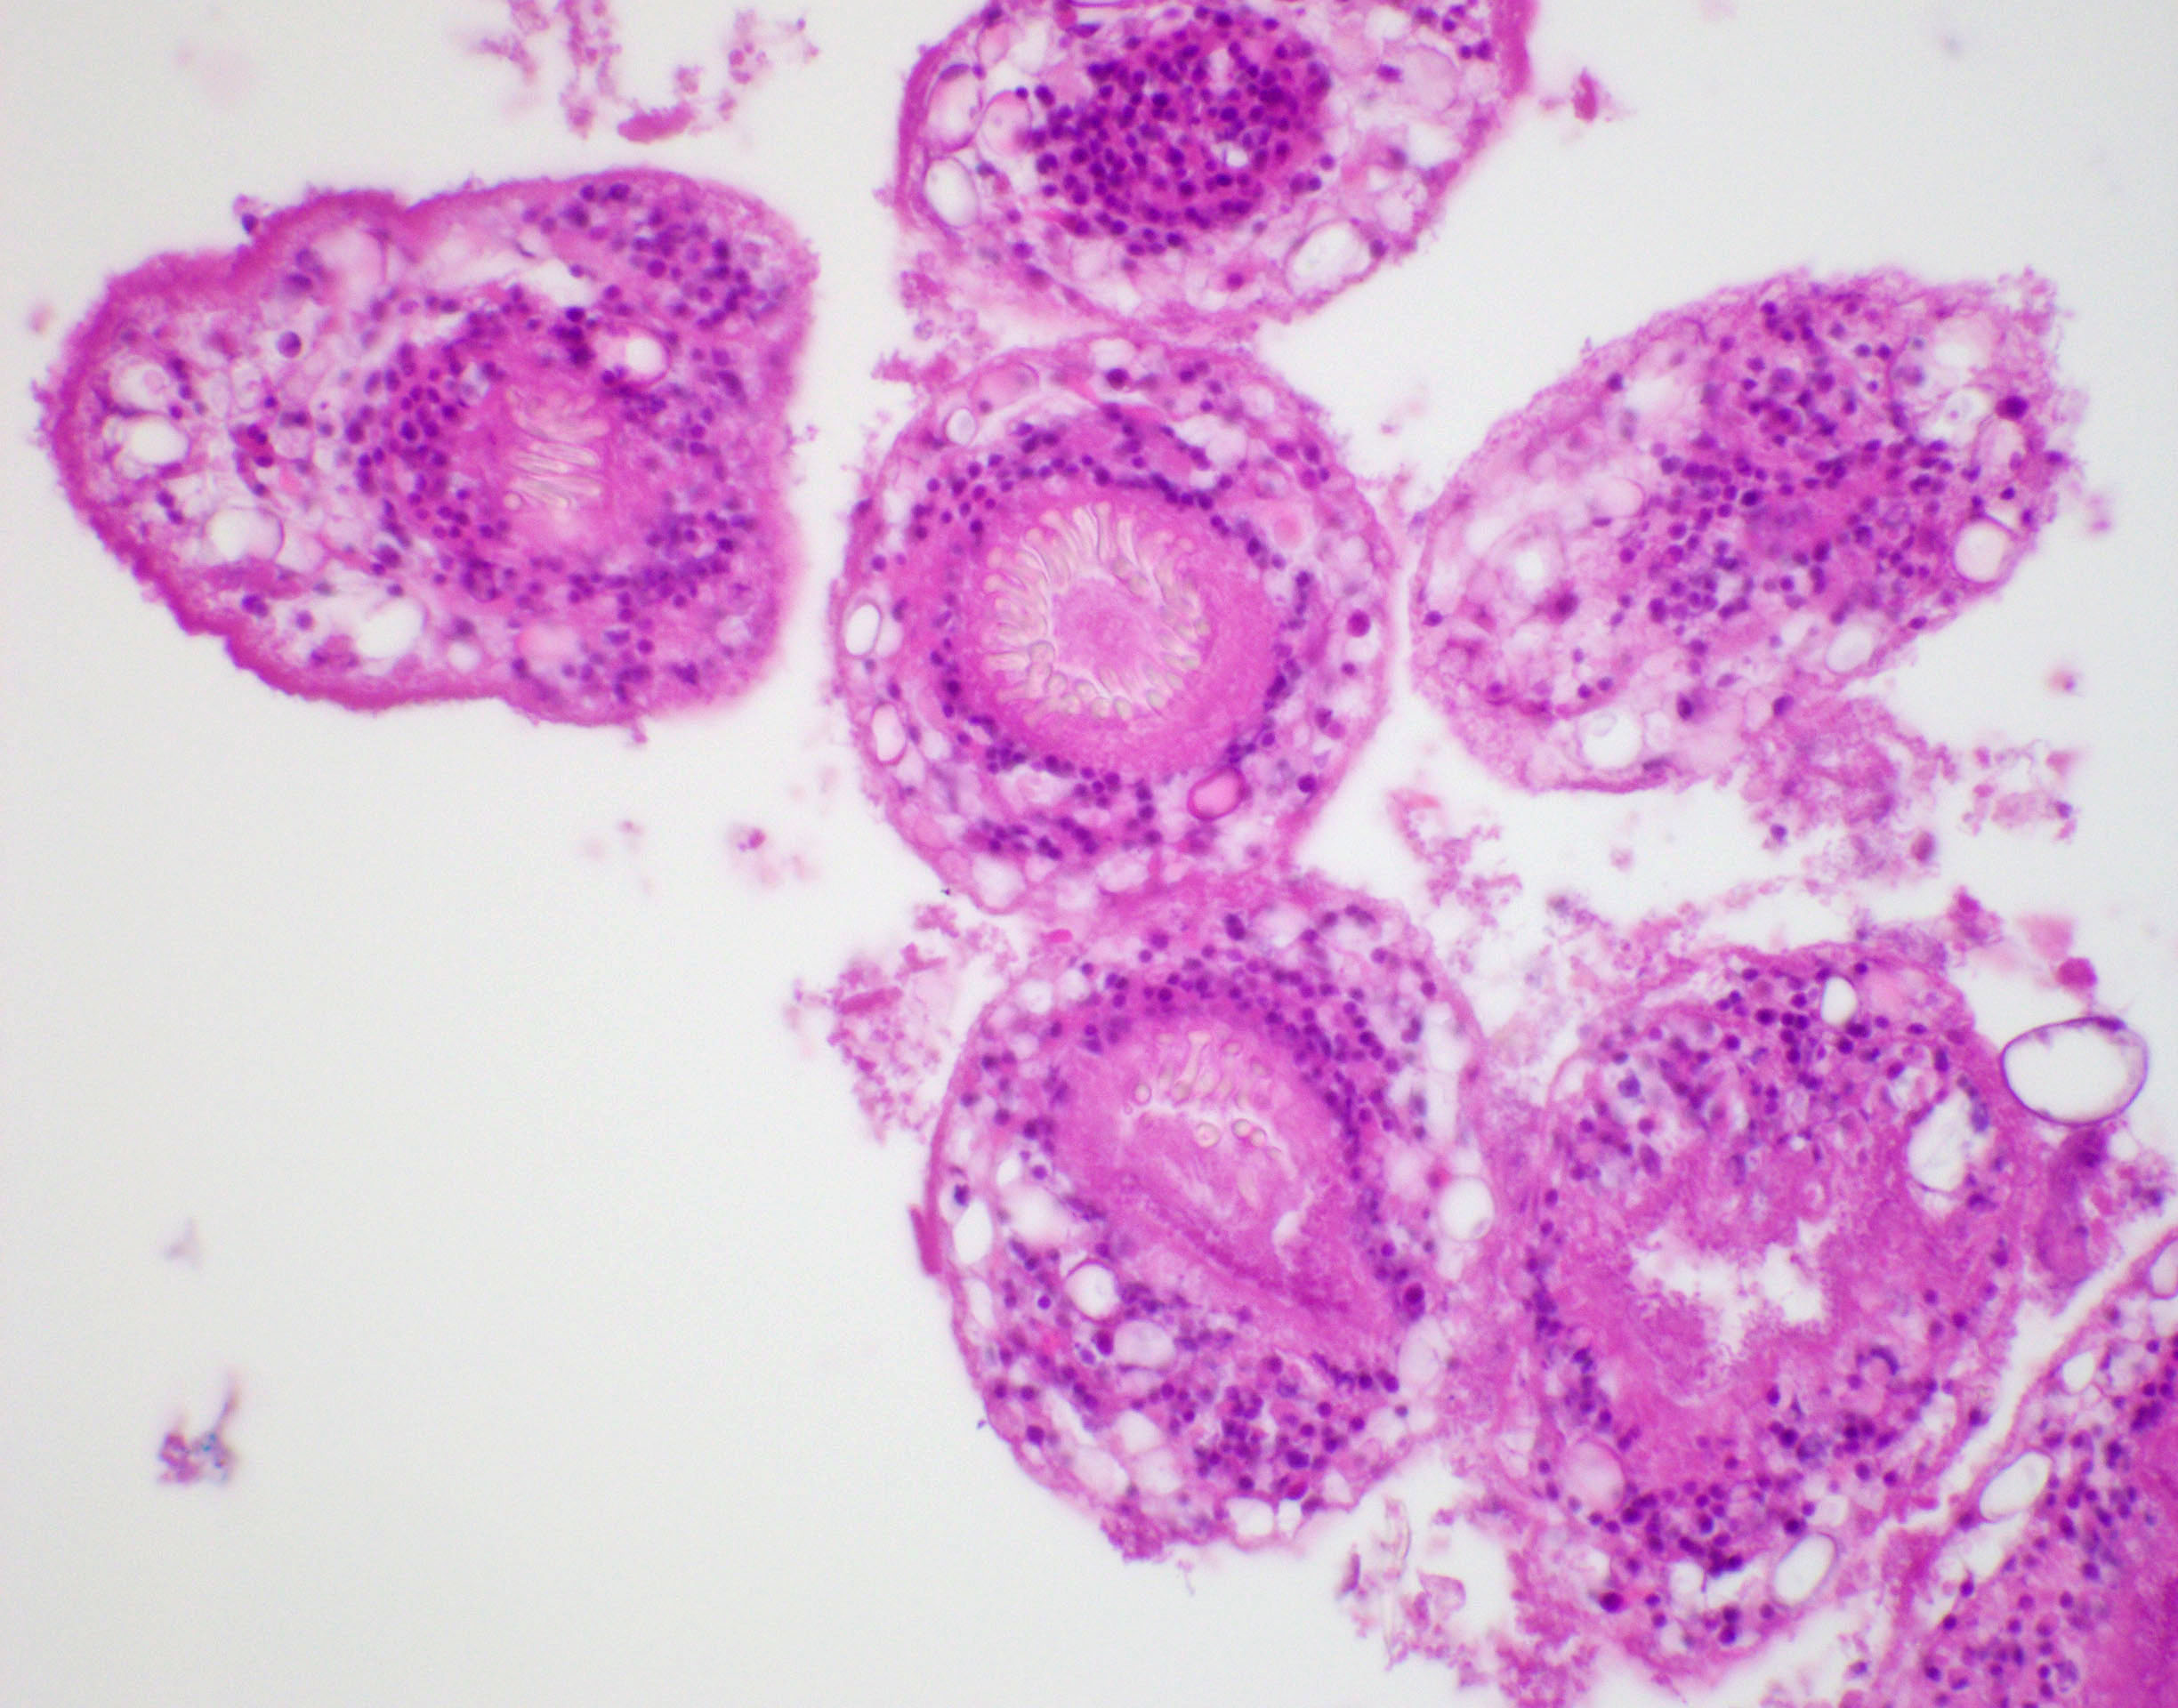

Microscopic (histologic) description

- E. granulosus

- Cyst wall has 3 structural components:

- Outer acellular laminated membrane (1 mm thick)

- Germinal membrane (a transparent nucleated lining)

- Protoscolices, attached to the membrane and budding from it

- Protoscolices are ovoid and contain hooklets (birefringent under polarized light) and a sucker

- Outer fibrotic layer with granulation tissue with increased eosinophils also exists

- Cyst wall has 3 structural components:

Microscopic (histologic) images